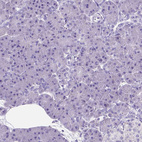

Immunohistochemistry analysis in human seminal vesicle and pancreas tissues using HPA045064 antibody. Corresponding PTGES RNA-seq data are presented for the same tissues.